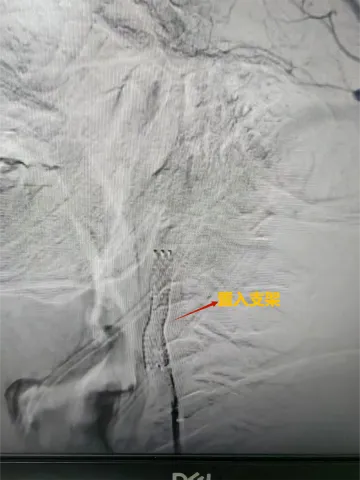

邵阳日报·邵阳新闻在线讯(通讯员 林海英)10月10日,神经内科一区收到了一封感谢信,来自一位因颈动脉狭窄进行了支架置入术的患者。患者从入院检查到完成手术康复出院仅用时三天,邵阳市中心医院神经内科介入团队让患者体验到了“微创手术+快速康复”的惊喜。

颅内动脉狭窄是导致缺血性脑卒中的重要原因,而支架植入术是有效的预防手段。该手术操作极其精细,容错率低。近年来,随着国家对于卒中防治体系建设的投入,该院神经内科介入团队手术量持续增长,技术的熟练度带来了手术成功率的显著提升和并发症发生率的明显下降。